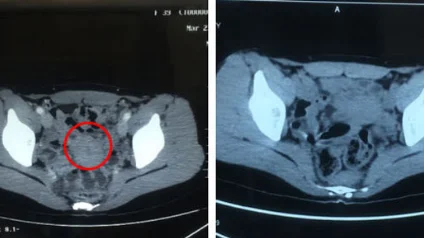

• Hình ảnh CT trước và sau điều trị

Nguyễn Thị Giang Thanh

Bà Nguyễn Thị Giang Thanh, 58 tuổi, đến từ Hà Nội, Việt Nam, bị ung thư vú tái phát vào tháng 6 năm 2023, đồng thời xuất hiện di căn hạch vùng cổ và hạch trung thất. Trước đó, bà từng điều trị tại Bệnh viện K ở Việt Nam nhưng hiệu quả không như mong đợi.

Đến tháng 1 năm 2025, sau khi được điều trị tại bệnh viện chúng tôi bằng liệu pháp can thiệp kết hợp cấy hạt phóng xạ, một phần khối u di căn đã thu nhỏ tới 80%, thậm chí có khối đã “biến mất” hoàn toàn.